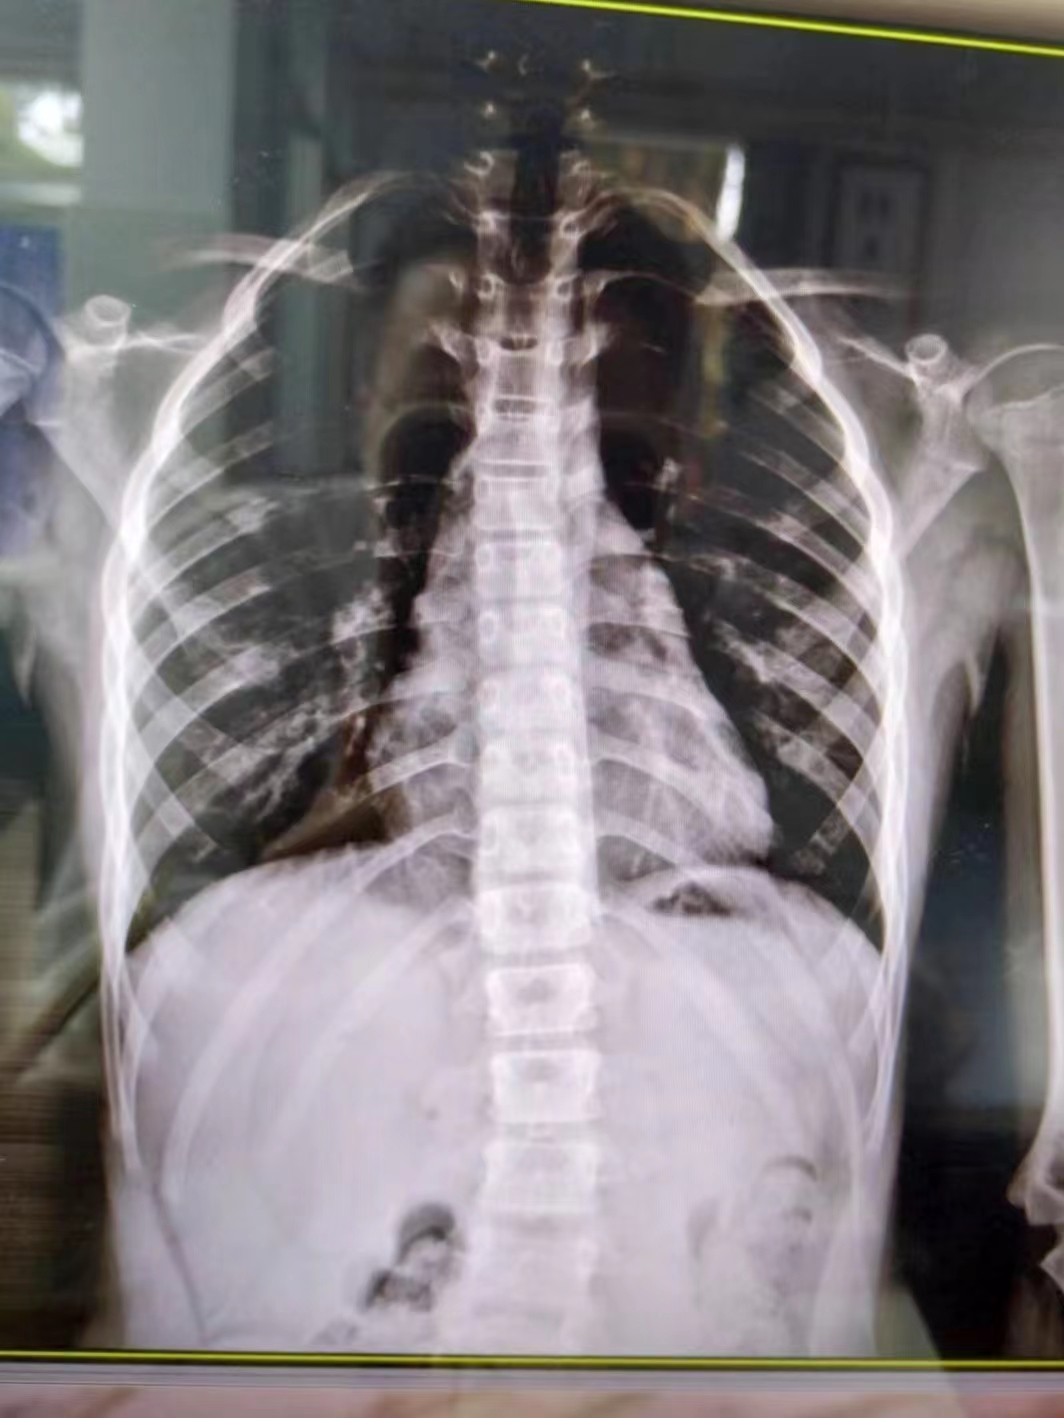

在康復醫(yī)學科,徐棟醫(yī)生通過X線片確認小朋友患有脊柱側(cè)彎,“其實肉眼也可以看到小朋友的脊柱有彎曲弧度,家長的擔心是正確的。”

幸運的是,由于媽媽發(fā)現(xiàn)及時,小朋友的情況無需手術(shù)治療,經(jīng)過7次整脊手法按摩治療后,側(cè)彎明顯好轉(zhuǎn)。

Adam前屈試驗:直立位雙手合十,體前屈90度,觀察兩側(cè)肩胛骨高低,若呈現(xiàn)“剃刀背”,則凸側(cè)表示脊柱向右側(cè)彎。若發(fā)現(xiàn)異常,盡快拍攝全脊柱正側(cè)位X線片,必要時行全脊柱MRI檢查排除椎管內(nèi)腫瘤。